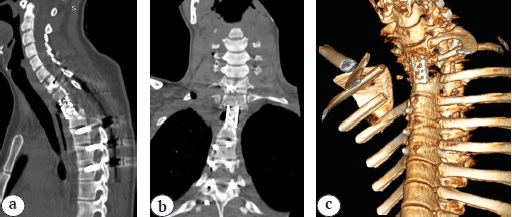

The patient was verticalized on day 3 postoperative 2; the drainage was removed on day 2. The total period of inpatient treatment was 24 days. In the neurological status upon discharge, complete regression of motor disorders was noted with functional restoration of the lower extremities to type E according to the Frankel scale. The results of the control CT are presented in Figure 5.

Fig. 5. CT images at the time of hospital discharge: a — sagittal view: anterior fusion by titanium mesh-cage with autologous bone graft and posterior screw fixation, correct implant position with angular kyphosis correction; b — frontal view: upper right lung lobe aerated, post-cystic resection cavity; c — 3D scan: right side 1–2nd rib costotransverseectomy, anterior Th1-3 fusion by titanium mesh-cage